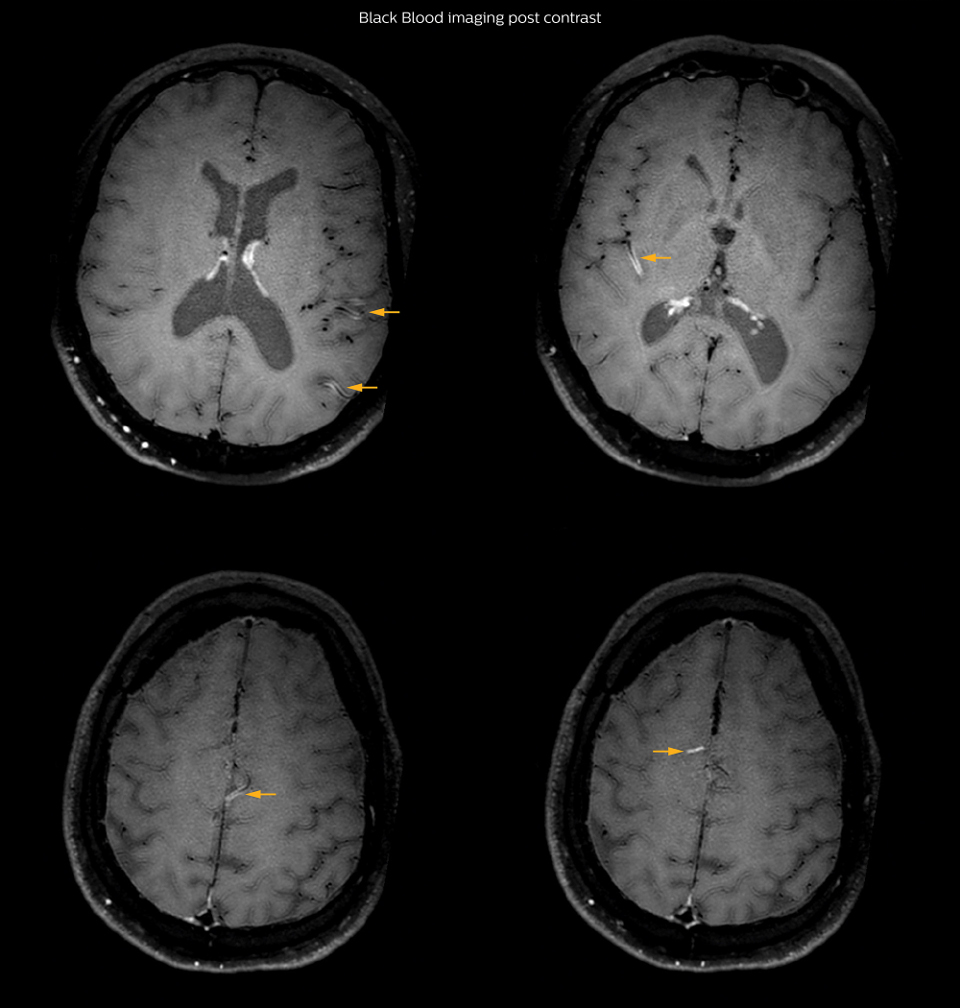

On FLAIR images we can see some nonspecific high signal abnormalities in frontal white matter bilaterally. On DWI we can see acute ischemic lesions which appear with high signal intensity. Arrows show vessel wall enhancement which appears concentric and homogeneous in different cerebral territories.

Arrows show vessel wall enhancement which appears concentric and homogeneous in different cerebral territories.

So, we decided to perform Black Blood imaging. The presence

and the pattern of vessel wall enhancement on Black Blood

imaging, can help us to determine the etiology of the lesion.

Many studies have shown that Black Blood imaging can help

differentiate vasculitis from other causes of vasculopathy, such as

atherosclerosis, with a high specificity [1-3]. In an atherosclerotic

lesion, vessel wall thickening and enhancement are usually eccentric,

while in vasculitis the wall thickening and enhancement are usually

concentric, homogenous, and in a long portion of the vessel.